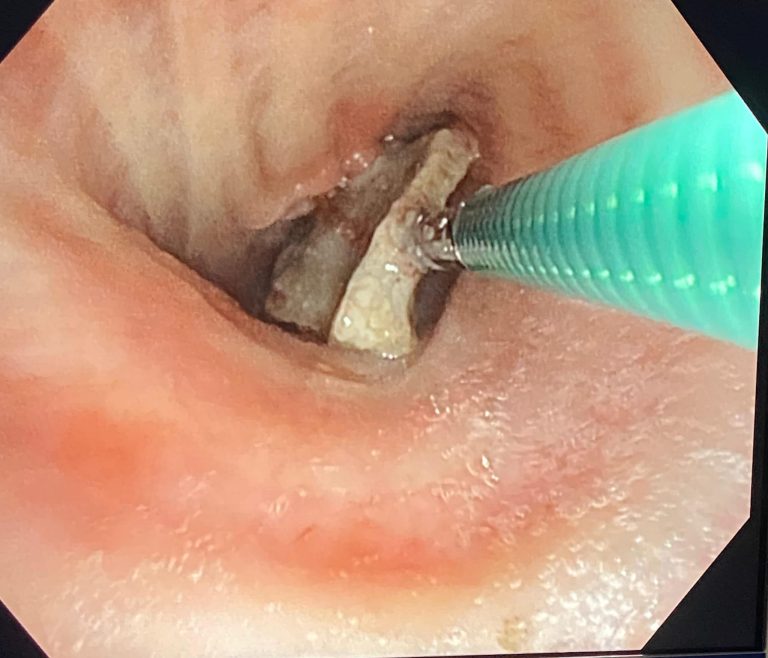

FOTO: Os de peste un centimetru extras din plămânul unui pacient la Spitalul de Pneumoftiziologie Sibiu